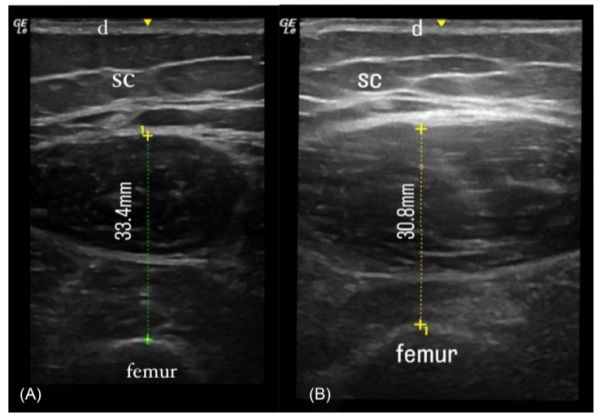

图1 28岁男性(BMI = 26.8 kg/m2)轴向超声图像。

30名血友病A患者和26名成年男性志愿者参加了这项研究。检测肌少症时,将生物电阻抗分析(BIA)得到的阑尾骨骼肌质量(ASM)除以身高的平方(m2),得到阑尾骨骼肌质量指数(ASMI)值。双下肢大腿采用改良超声紧度调整比(STAR)法测量,该方法由超声测量的双侧股直肌和股中间肌厚度相加得到。用测力仪测量手和股四头肌肌力(MS)。采用步行速度(WS)、定时起身测试(TUGT)、5次重复坐立测试(5RSTS)和6分钟步行测试(6MWT)来测定身体性能。血友病关节健康评分(HJHS)和血友病早期关节病变超声检查(HEAD-US)也用于评估肌肉骨骼系统。